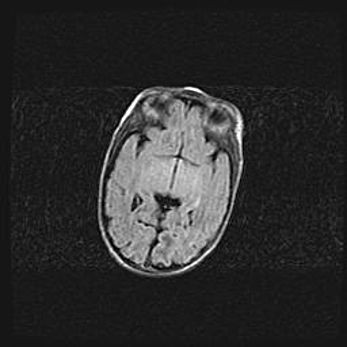

Аномалия Денди-Уокера. Признаки гипоплазии мозолистого тела.

Возраст: 5 месяцев 3 дня

Вес: 5550 г

Пол: мужской

Окружность головы: 39 см

Срок гестации: 40 недель

Аномалия Денди-Уокера – это порок развития головного мозга, для которого характерна триада симптомов: гипотрофия или аплазия червя мозжечка и/или полушарий мозжечка, расширение четвёртого желудочка с формированием ликворной кисты задней черепной ямки, гипертензионная гидроцефалия различной степени.

Гипоплазия мозолистого тела относится к дефектам внутриутробного этапа развития мозговой ткани, возникающим в процессе закладки структур головного мозга, что происходит на начальных этапах развития эмбриона.